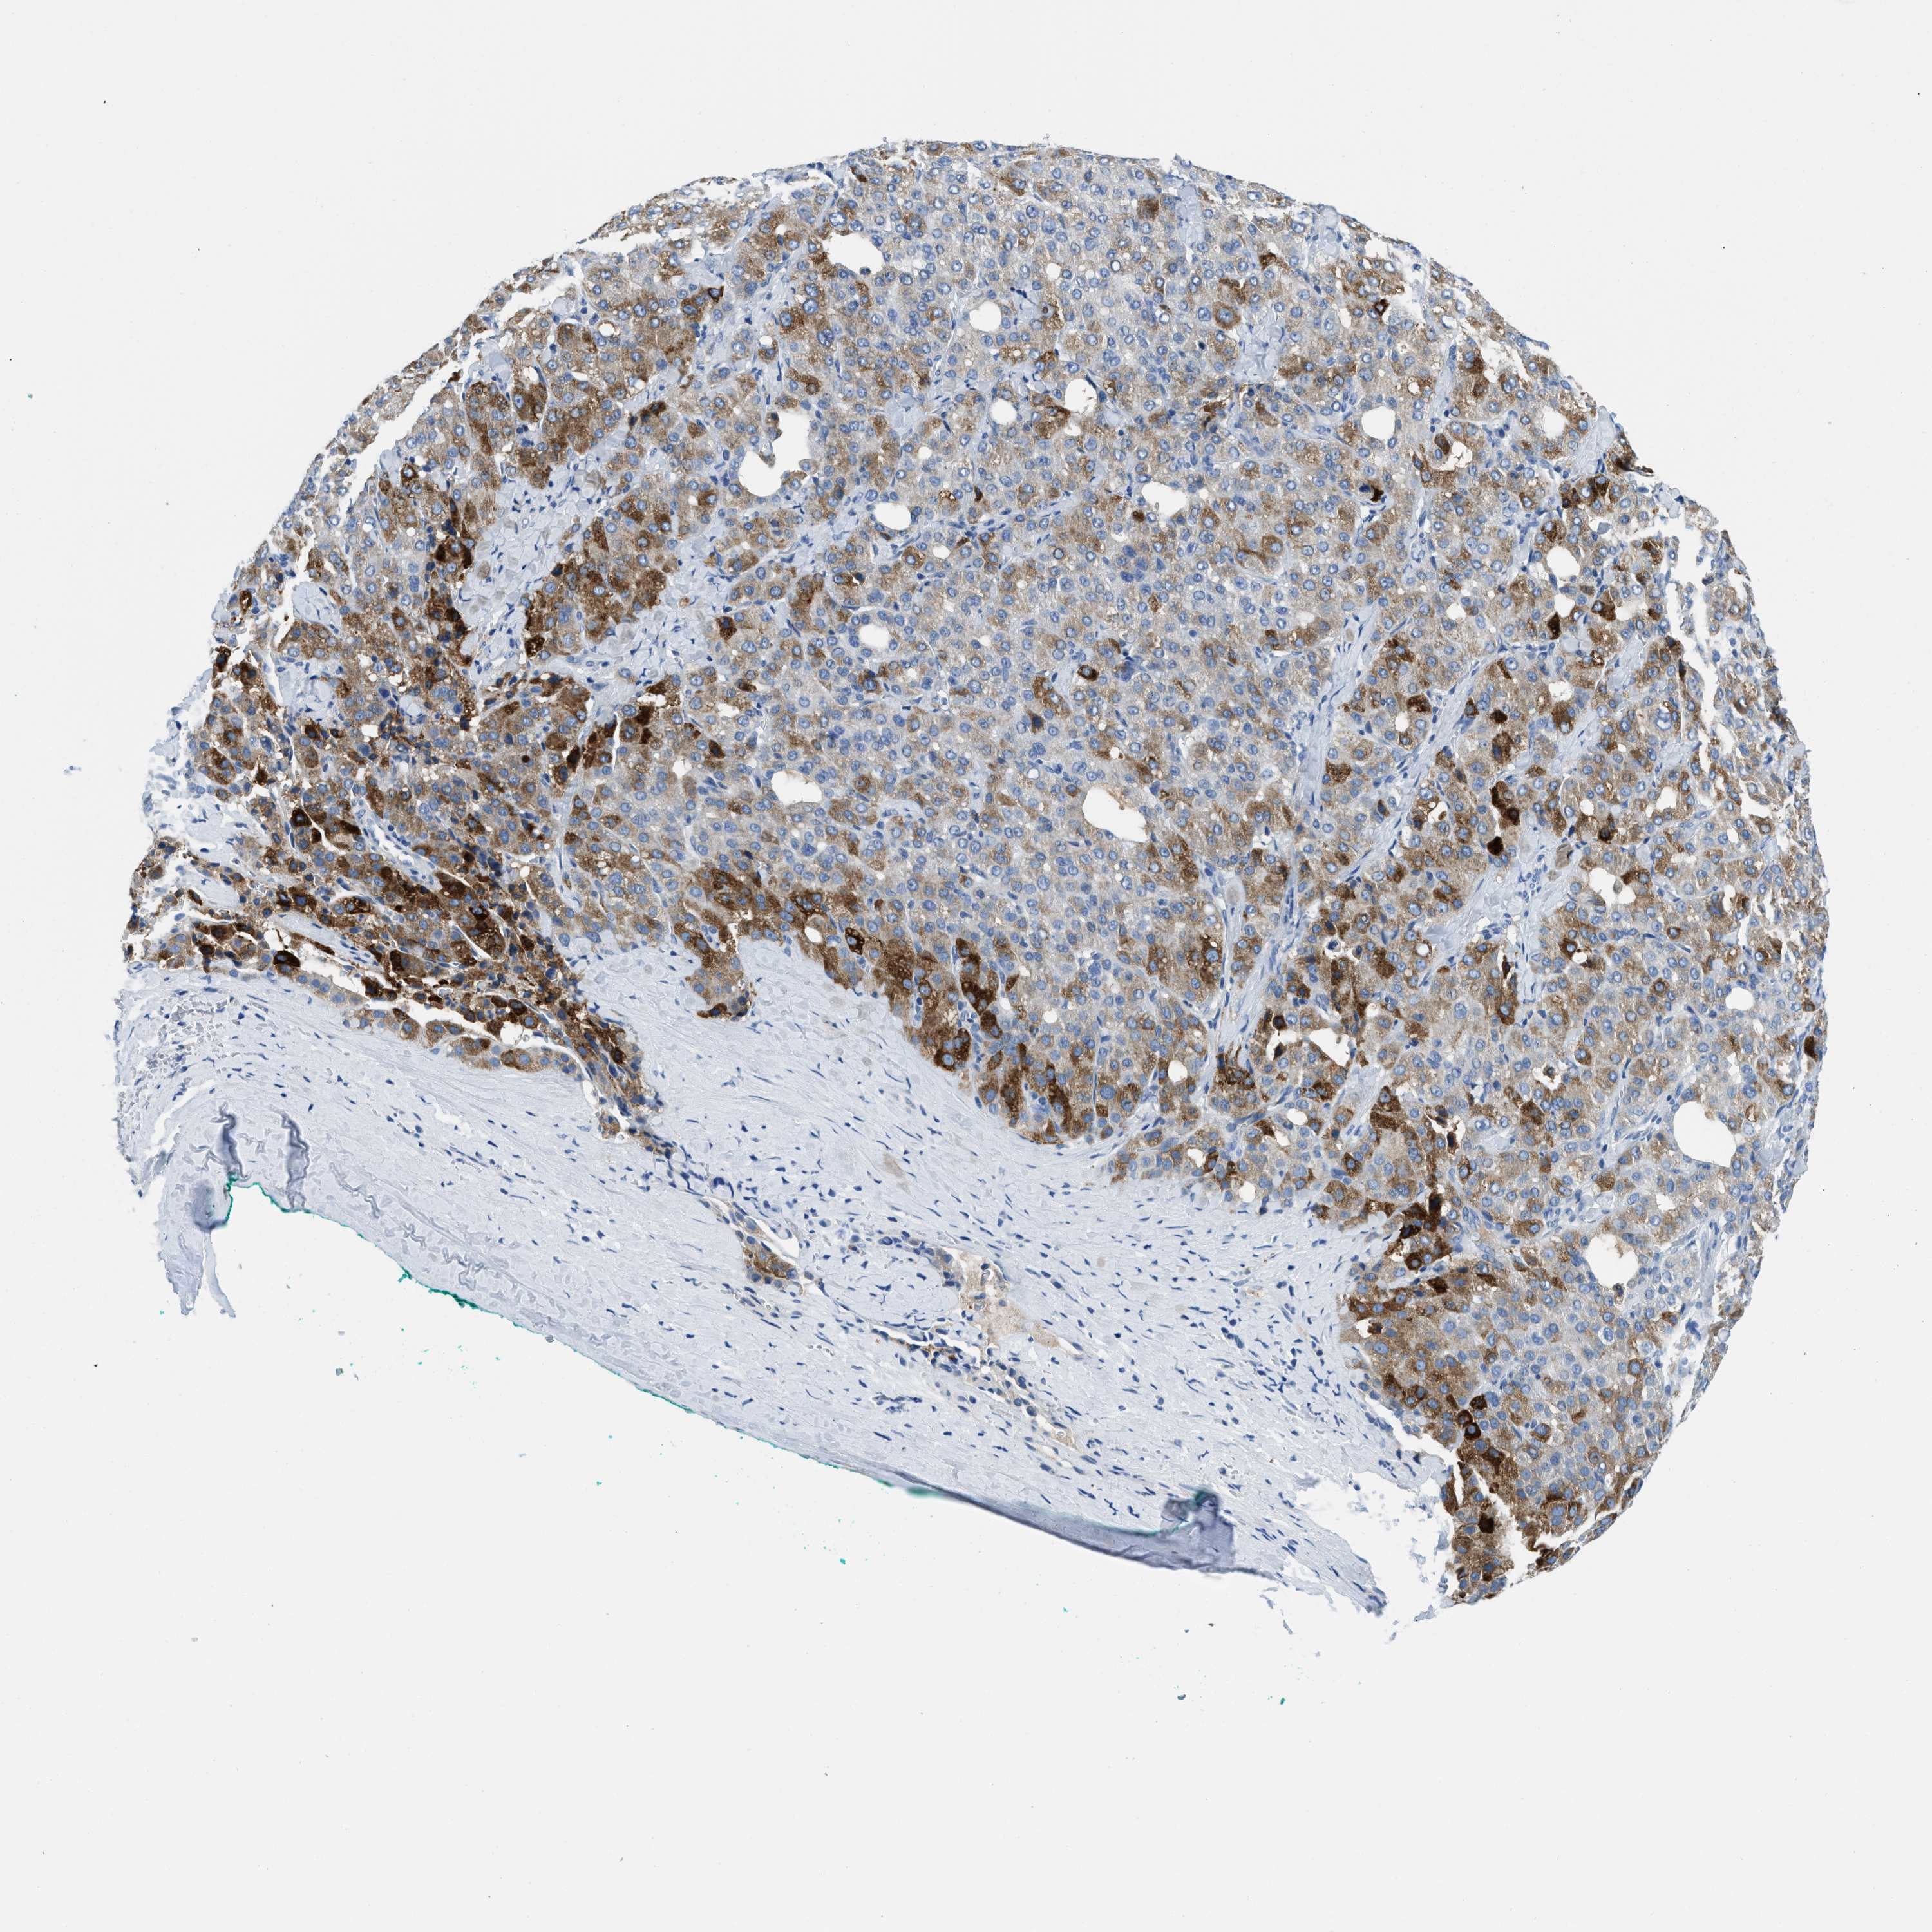

LIVER CANCER - Protein expressioni

A mouse-over function shows sample information and annotation data. Click on an image to view it in a full screen mode. Samples can be filtered based on level of antibody staining by selecting one or several of the following categories: high, medium, low and not detected. The assay and annotation is described here.

Antibody stainingi

Antibody staining in the annotated cell types in the current human tissue is reported as not detected, low, medium, or high, based on conventional immunohistochemistry profiling in selected tissues. This score is based on the combination of the staining intensity and fraction of stained cells.

Each image is clickable and will lead to virtual microscopy that enables deeper exploration of all samples and also displays staining intensity scores, fraction scores and subcellular localization as well as patient and tissue information for each sample.

Antibody HPA002027

Antibody CAB016782

Staining

High

Medium

Low

Not detected

Intensity

Strong

Moderate

Weak

Negative

Quantity

>75%

75%-25%

<25%

None

Location

Nuclear

Cytoplasmic/membranous

Cytoplasmic/membranous,nuclear

Carcinoma, Hepatocellular, NOS

Cholangiocarcinoma